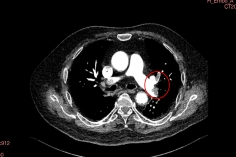

患者杨先生,70岁,因“腰背部疼痛3小时”急诊入院。完善增强CT显示双侧肺动脉主干及分支大面积栓塞,血栓长度超过10cm,右心室明显扩张,肺动脉压力高达60mmHg(正常值<25mmHg)。完善下肢静脉超声证实存在深静脉血栓(DVT)。

患者由于血流动力学不稳定,收缩压下降,氧饱和度仅72%(未吸氧状态下),心脏负荷大,随时可能引发心脏骤停,病情十分凶险。

手术过程分三步走:精准定位、机械取栓、联合防治。术中取出暗红色血栓,同期植入可回收下腔静脉滤器预防再栓塞,手术圆满完成。术后启动利伐沙班+低分子肝素桥接抗凝方案。

术后造影双侧主干未见明显血栓

术后,患者肺动脉压力从60mmHg降至35mmHg,氧饱和度恢复至96%。患者恢复健康后已出院。